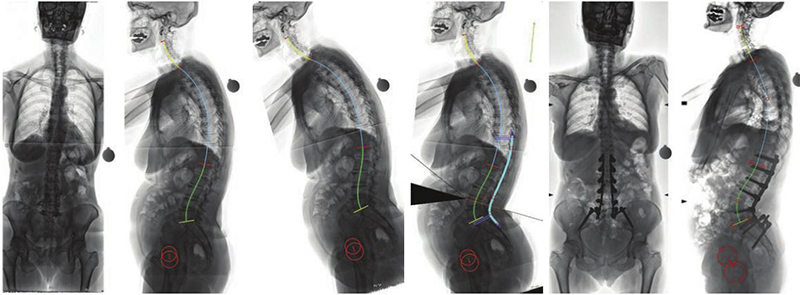

Η αντιμετώπιση των παραμορφώσεων της σπονδυλικής στήλης των ενηλίκων, ένα πολύ ιδιαίτερο και δύσκολο χειρουργικό πρόβλημα, βασίζεται πλέον στον ακριβή, γεωμετρικό, τρισδιάστατο προεγχειρητικό σχεδιασμό, με τη βοήθεια υπολογιστικών προγραμμάτων χειρουργικού σχεδιασμού. Μέσω αυτής της τεχνικής, σχεδιάζεται με απόλυτη ακρίβεια η χειρουργική επέμβαση ενώ παράλληλα προκατασκευάζονται και υπάρχουν διαθέσιμα στο χειρουργείο τα εξατομικευμένα, διαφορετικά για κάθε διαφορετικό ασθενή, υλικά σπονδυλοδεσίας.

Επιπλέον, με τη χρήση της διεγχειρητικής τρισδιάστατης νευροπλοήγησης (ρομποτική χειρουργική της σπονδυλική στήλης), είναι εφικτή η ταχύτατη, με ακρίβεια και ασφάλεια, εμφύτευση των υλικών οστεοσύνθεσης και η πραγματοποίηση ακόμα και των πιο λεπτών χειρουργικών επεμβάσεων, σε όλες τις περιοχές της σπονδυλικής στήλης, από τον αυχένα έως και το ιερό οστούν. Η διόρθωση της παραμόρφωσης ελέγχεται διεγχειρητικά ενώ ο χειρουργός έχει τη δυνατότητα επιπλέον τροποποιήσεων την ώρα του χειρουργείου, ώστε να πετύχει το καλύτερο δυνατό αποτέλεσμα.

Διεγχειρητική τρισδιάστατη απεικόνιση σε πραγματικό χρόνο (ρομποτική χειρουργική), για την ασφαλή και ακριβή τοποθέτηση των χειρουργικών υλικών σπονδυλοδεσίας (α), αντιμετώπισης όγκου στον αυχένα - σπονδυλοσπλαστική (β, γ), και οστικής μετάστασης στη λεκάνη - θερμική εκτομή του όγκου με ραδιοσυχνότητες(δ)